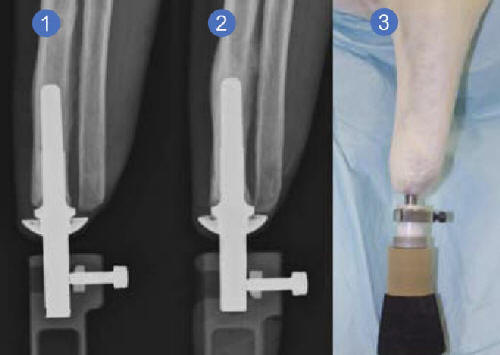

Sfortunatamente, anche in alto la funzionalità della protesi non può sempre fornire al paziente la mobilità che possedeva prima. Oltre alla sensazione soggetto alieno spesso agisce come una distrazione o anche un fattore repulsivo che non consente di percepire protesi in sostituzione completa di un braccio o una gamba persi. il tuttavia, la tecnologia intraosseo può risolvere questo problema protesi per amputazione transcutanea “(ITAP), implicando un approccio radicalmente diverso ai principi della protesi. insieme, da scienziati britannici dell’Università di Londra e Era il Royal National Orthopaedic Hospital È stato progettato un modello di una protesi del piede unica. suo una caratteristica distintiva è il metodo di attaccamento selezionato. Invece di indossare una gamba artificiale, fissandola amputazione del corpo, costruzione ITAP utilizzando viene impiantato un elemento metallico appositamente progettato attraverso la pelle, collegando così la protesi direttamente a osso umano.

Foto da fonti aperte Va notato immediatamente che espresso il principio di usare un impianto come il legame tra l’arto artificiale, l’osso e il morbido i tessuti non sono affatto nuovi. Tuttavia, gli autori del progetto sostanzialmente finalizzato il modello di un impianto metallico per la sua velocit� adattamento nel corpo. Nel luglio di quest’anno è stata effettuata la prima selezione. persone che lo scopriranno durante le prove pratiche vantaggi, caratteristiche e possibili svantaggi versione presentata della protesi. Secondo le informazioni disponibili, a questo momento già amputato 20 in acciaio possessori di una nuova gamba artificiale. La comodità degli impianti ITAP conferma Mark O’Leary, che ne divenne il proprietario nel 2008. Ha detto che un arto perduto è come tornò e la sentì completamente. A sostegno di questo O’Leary con una gamba protesica riuscì a conquistare Kilimanjaro e molti altre cime montuose. Essere tra i primi venti pazienti, che sperimenterà un più perfetto e avanzato in termini tecnici modello di piano, Mark O’Leary già in questa fase notato insolitamente sensazioni reali mentre ti muovi. Per evitare il rifiuto organismo di materiale estraneo, sviluppatori durante la creazione l’impianto ha sfruttato il segno distintivo della struttura … corna cervi. Questa formazione ha una struttura porosa unica, che gli scienziati hanno preso come base. Il concetto di un’idea è in modo che le cellule della pelle si fondano con un corpo estraneo, penetrando pori per analogia, come accade con le corna di cervo. Creato da i tessuti di tenuta devono riempire buchi e ostruire la formazione di infezioni batteriche e aiuta anche in modo affidabile sistemare la struttura in modo naturale. Nonostante un numero benefici come l’assenza di irritazione dolorosa in atto articolazioni di una protesi convenzionale e gambe a causa di attrito, e ha inoltre elaborato al massimo livello il feedback tra ITAP piede e uomo, la tecnologia ha i suoi svantaggi. su In sostanza, una tale protesi implica una volta e finale installazione. Il suo proprietario non sarà semplicemente in grado di rimuovere in modo indipendente progettare.